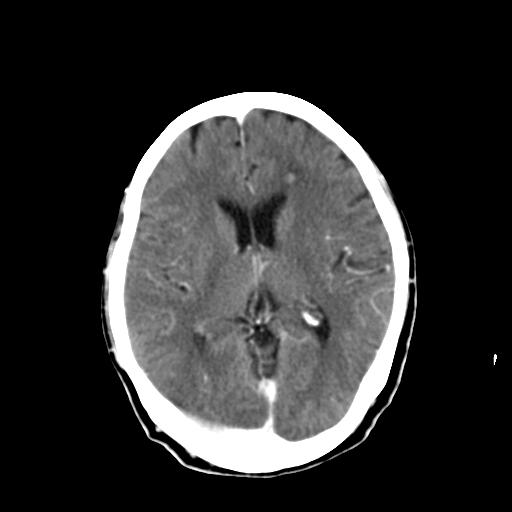

前两张头颅片子是平扫,请问能否考虑机化性肺炎或者间皮瘤?

本例颅内见多发大小不等高密度灶,有强化及水肿;另外,胸锁关节层面可能是第四胸椎及右侧肋骨起始部骨质欠连续,椎旁软组织肿胀,建议调骨窗观察。

右侧胸膜间皮瘤,双肺大泡,颅内多发转移(右顶叶、左侧侧脑室前角放射冠区)并出血。

左侧额叶及右顶叶实质内病灶首先应该考虑是转移性肿瘤伴出血{结合胸部强化}.

支持肺癌并脑内多发转移并出血;